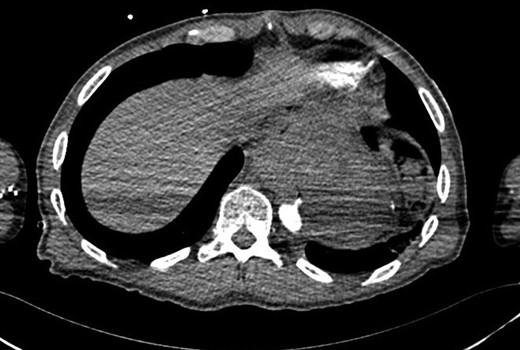

He re-presented with hypovolaemic shock and massive haematemesis four months later. A diagnosis of AEF was again confirmed on CTA (Fig. 2), just proximal to the previous aortic stent graft. He again had emergency percutaneous TEVAR covering the descending aorta from the level just below the left subclavian artery to just proximal to the celiac artery. Again, he was offered definitive surgery, but he was still not keen to have this at that time.

CT aortogram showing the extravasation of contrast from the aorta just proximal to the stent graft.